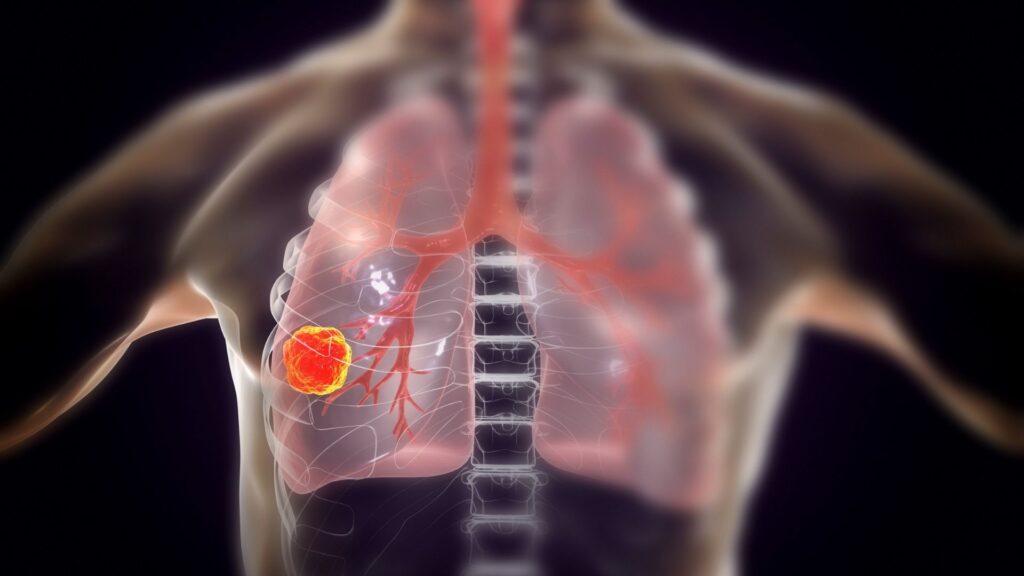

سرطان الرئة هو أحد أكثر أنواع السرطان فتكًا في العالم، وغالبًا ما يُشار إليه بالعدو الصامت نظرًا لعدم ظهور أعراض واضحة في مراحله المبكرة. ومع ذلك، يمكن الوقاية منه إلى حد كبير من خلال اتخاذ خطوات بسيطة لتقليل المخاطر.

سرطان الرئة يمكن الوقاية منه إلى حد كبير من خلال اتخاذ خطوات بسيطة لتقليل المخاطر. التوعية بأهمية الإقلاع عن التدخين وتجنب العوامل البيئية الضارة يمكن أن يساعد في حماية الأفراد من هذا العدو الصامت. الفحص المبكر والعلاج الفعال يمكن أن يحسنا من فرص النجاة بشكل كبير.